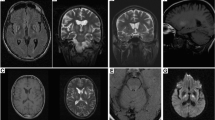

We reported the brain proton magnetic resonance spectroscopy (MRS) findings in 27 Wilson’s disease (WD) patients treated more than 6 years in neurological (nWD) and hepatic (hWD) subgroups. We investigated four hWD patients, with no improvement and eight with marked improvement; and eight nWD patients with marked improvement and seven with no improvement of clinical status. In nWD patients with improvement the MRS showed significantly higher Cho/Cr, Glx/Cr ratios levels. In hWD patients with no improvement the lower Cho/Cr and in nWD significantly lower NAA/Cr and higher Cho/Cr and Lip/Cr ratios were detected. In nWD patients with improvement the spectroscopic pattern, can be related to gliosis. In patients with no neurological improvement a persistent neuronal dysfunction can occur, perhaps as a result of copper or iron deposition.